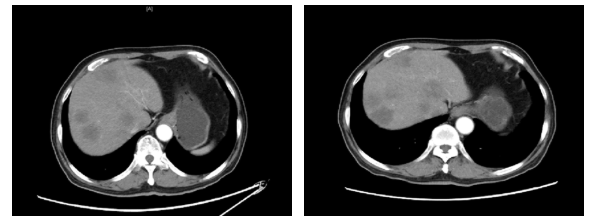

2020.1.5影像学评价:腹部CT:肝脏多发结节,较前增多增大,考虑进展(图3)。

图3. 腹部CT(左:2019.11.18,右:2020.1.5)